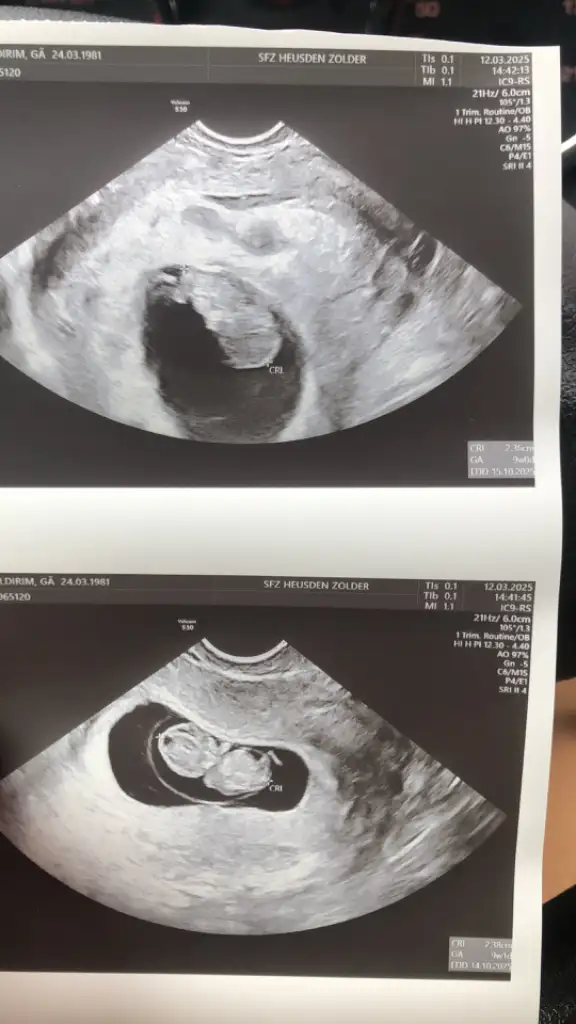

Eklentiler

• 9A0AC7C4-CCA6-4705-890C-6A7786EB0BCA.webp

9A0AC7C4-CCA6-4705-890C-6A7786EB0BCA.webp

25,3 KB · Görüntüleme: 49